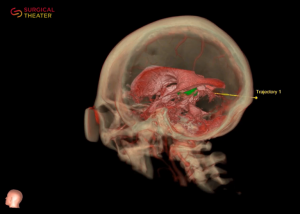

Surgical Theater

Seit März 2021 wird von Prof. Feigl erstmalig in Europa die Visualisierungsplattform Surgical Theater eingesetzt. Sie basiert auf den 3D-Technologien von virtueller und erweiterter Realität (virtual & augmented reality), welche es zulassen, dass insbes. komplexe neurochirurgische Operationen noch besser geplant und durchgeführt werden können.

NeurochirurgInnen können mit der neuen Technik Eingriffe bereits vor der eigentlichen Operation in virtueller Form und basierend auf den individuellen Besonderheiten der zu behandelnden Person Schritt für Schritt durchgehen.

So können die operativen Eingriffe optimal auf die individuelle Anatomie und Pathologie der PatientInnen abgestimmt und eine bestmögliche Operationsplanung umgesetzt werden. Überdies wird die 3D Neuronavigation („GPS für das Gehirn“) des Surgical Theaters auch während dem Eingriff eingesetzt, um ein größeres Maß an Kontrolle und Sicherheit für die PatientInnen zu gewährleisten.

Ein weiterer Vorteil für Patientinnen und Patienten ist die Verwendung der Plattform zum Zweck der Aufklärung. Dank der neuartigen Möglichkeiten einer „Reise in den eigenen Körper“ können die PatientInnen noch besser über die individuelle Erkrankungssituation und die geplanten Operationsschritte aufgeklärt werden. Sonst oft sehr abstrakte und für Fachunkundige schwer verständliche Informationen können so mit eigenen Augen erlebt werden, was zu einem besseren Verständnis führt, Ängste und Unsicherheiten abbaut und insgesamt das Vertrauen in das hochqualifizierte Operationsteam weiter stärken kann.